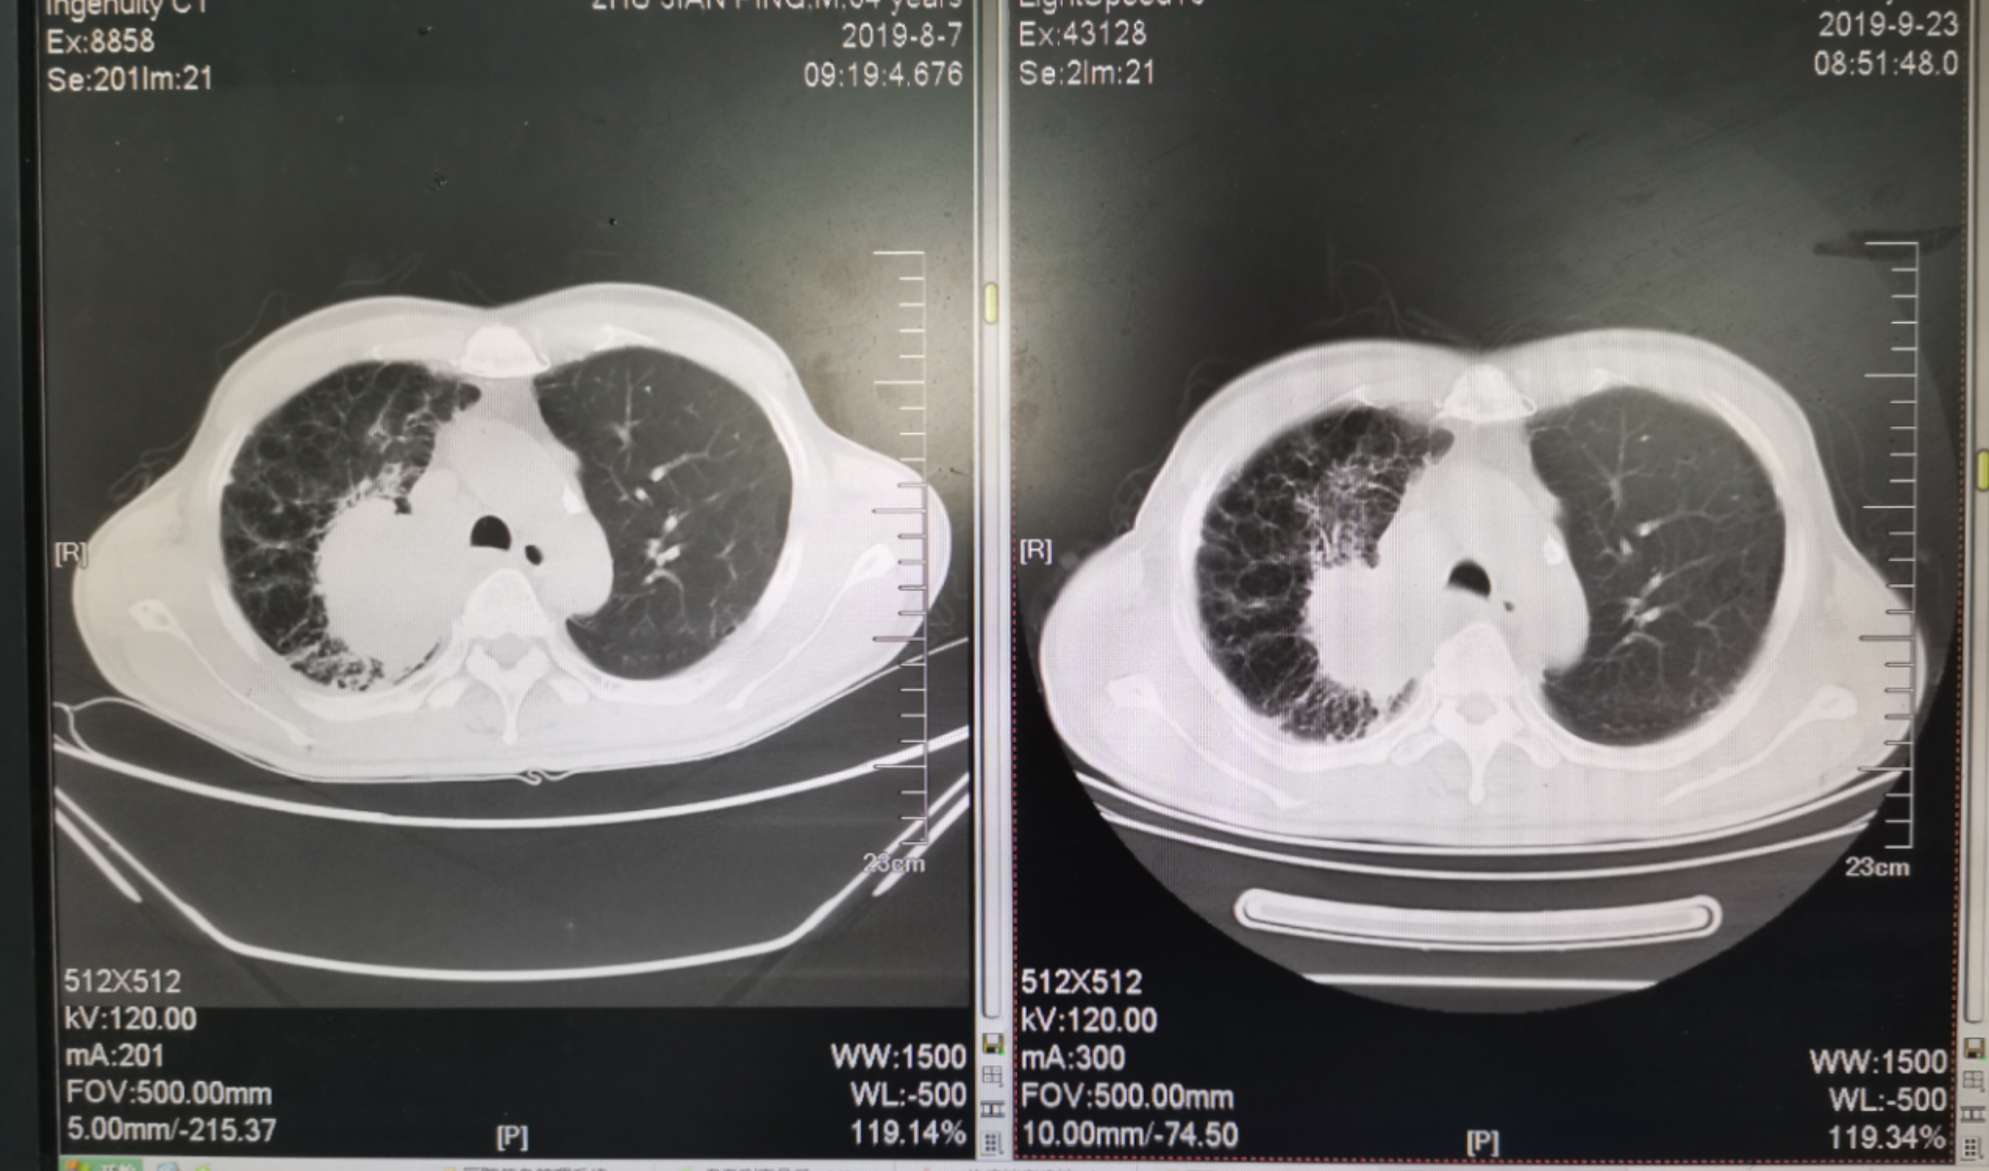

二化联合一k后复查ct对比

左边是上月化疗前的,右边是昨天拍的,今天上了第二次k药,准备明天第三期化疗。

我自己对着拍的,切面对的不是很准确,但大致上看的出来明显小了。

明显缩小